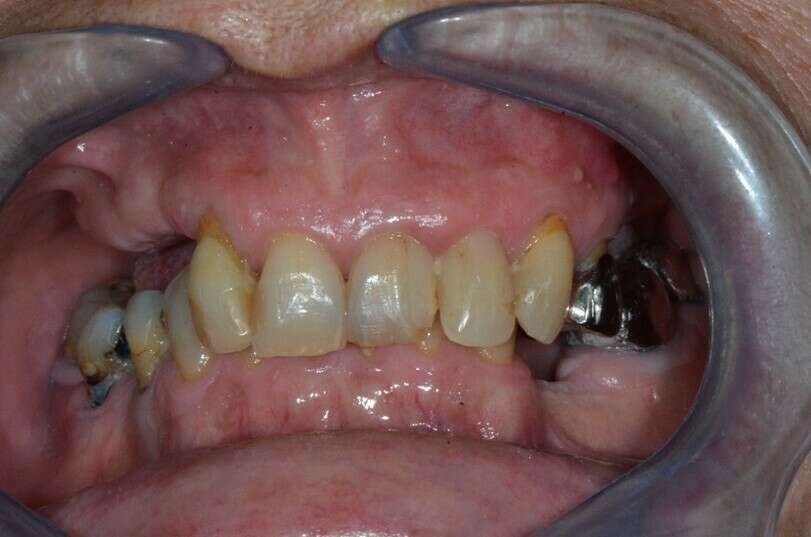

Patiente de 65 ans, sans problème de santé, venue consulter pour une réhabilitation complète.

La patiente ne peut plus mastiquer et le reste de ses dents maxillaires sont douloureuses.

Etat initial de la patiente photo et radiographie